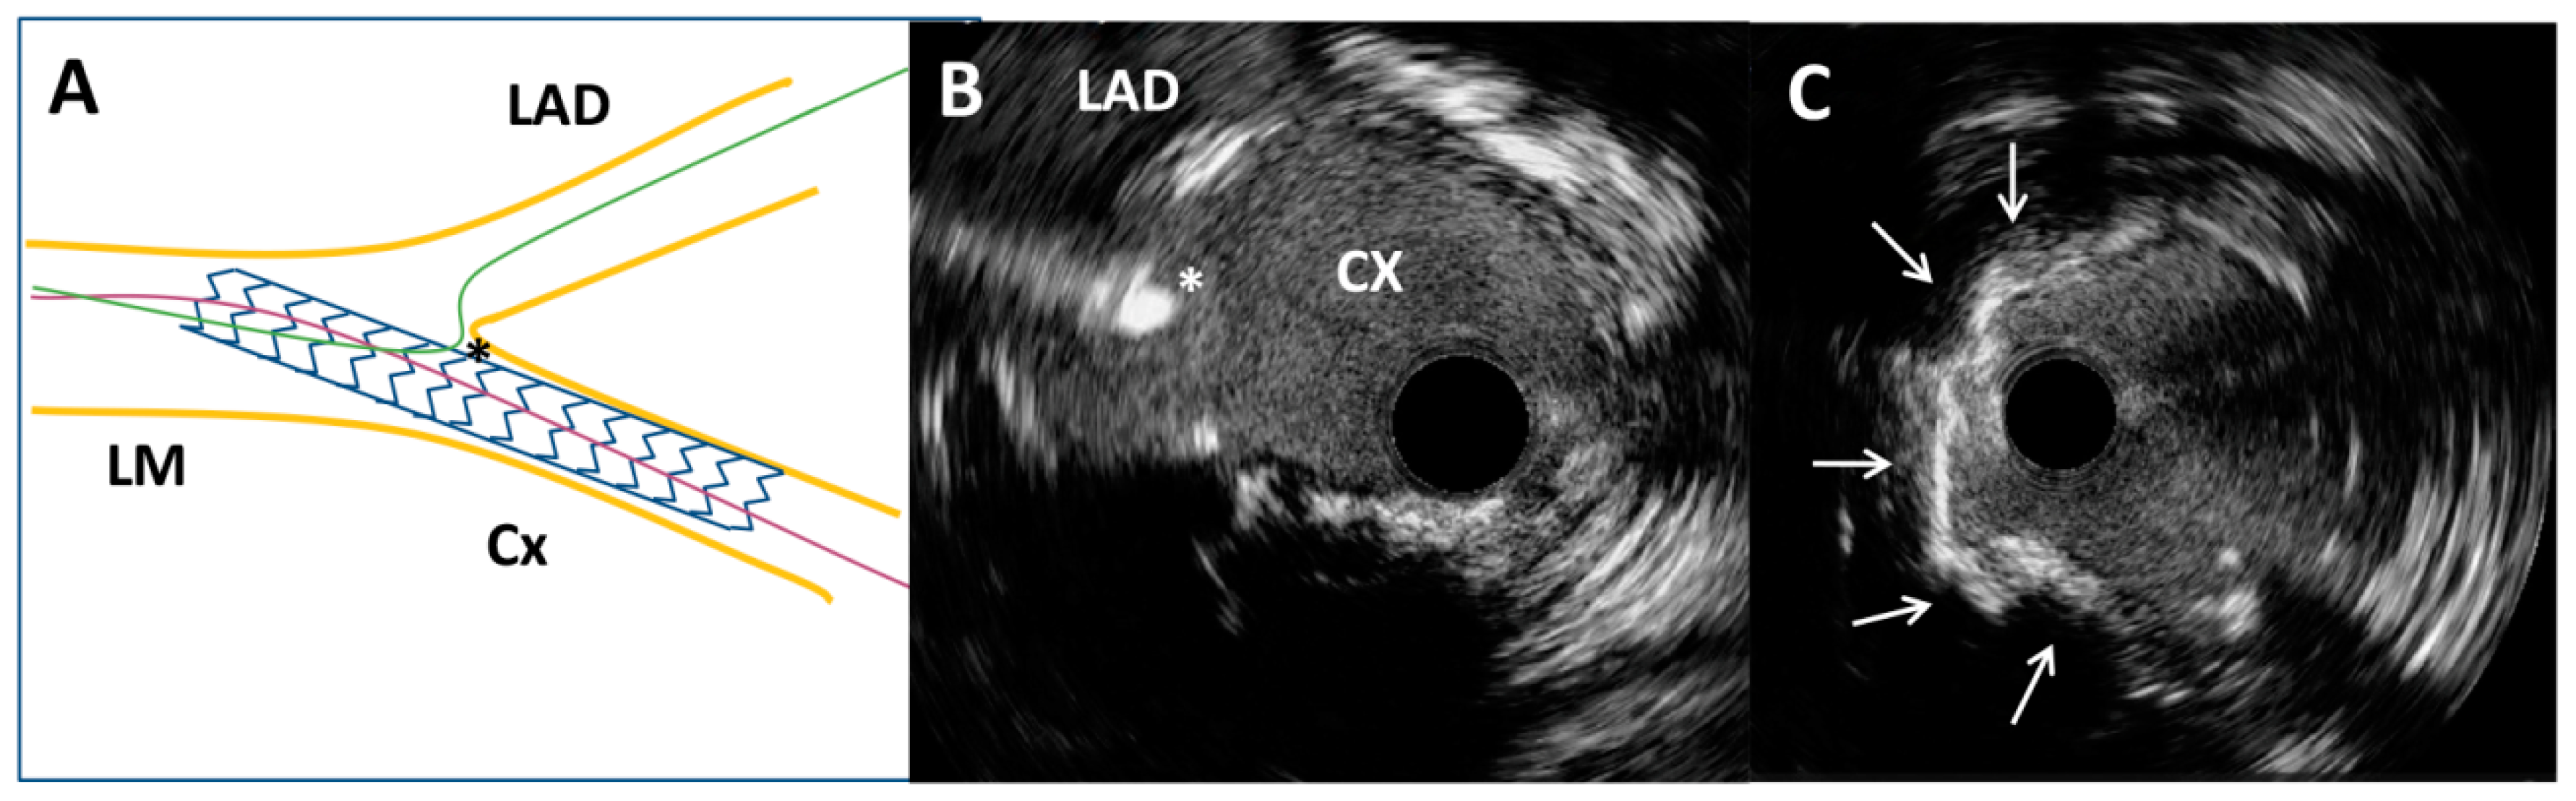

The Role of Intravascular Ultrasound in the Evaluation and Treatment of Free-Floating Stent Struts Following Inadequate Ostial Circumflex Stenting: A Case Report

2. Case Report